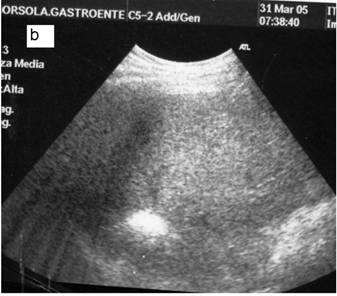

Fig 5

a: Ipoechoic nodule of the VII liver segment in a non cirrhotic liver pattern, normal hepatic vein. b: The same nodule after RF session.